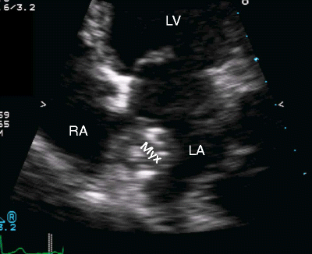

Fig. 3